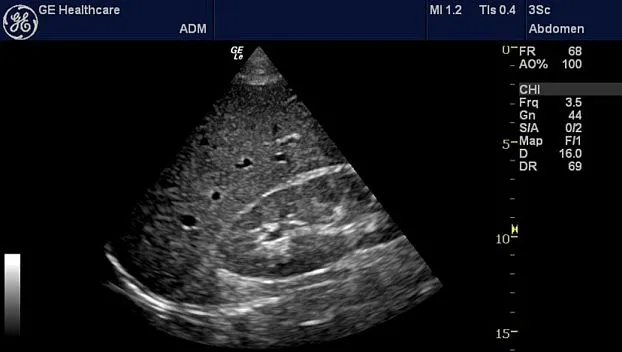

Клинические изображения

- Абдоминальные исследования

- C1-5-RS конвексный датчик, широкополосный, мультичастотный с диапазоном частот 2,0-5,0 МГц. Клиническое применение: Брюшная полость, урология, акушерство/гинекология, сосуды брюшной полости, скелетно-мышечные (включая бедро и позвоночник)

- 3Sc-RS секторный фазированный датчик, широкополосный мультичастотный с диапазоном частот 1,7-4,0 МГц. Клиническое применение: взрослая и детская кардиология, брюшная полость, акушерство, гинекология, плевра и глазницы